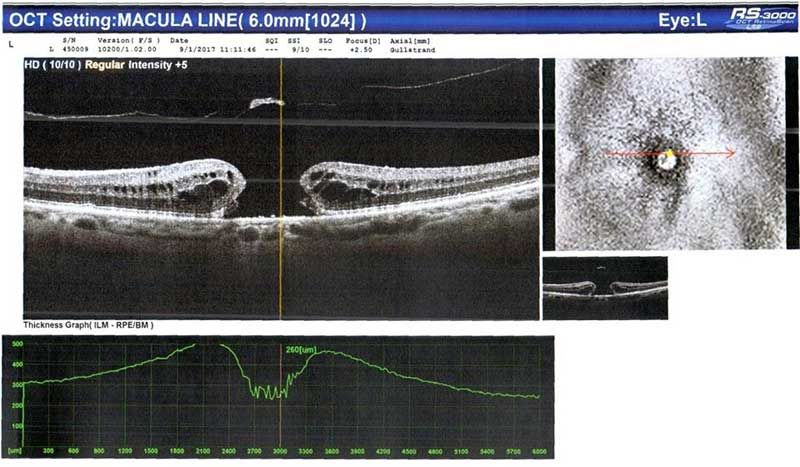

Το οφθαλμολογικό ιατρείο του Δρ. Γεροδήμου, στην Καλαμπάκα, είναι πλήρως εξοπλισμένο με μηχανήματα τελευταίας τεχνολογίας, που κάνουν απόλυτα ακριβείς μετρήσεις και διαγνώσεις. Ο ιατρός σάς παρέχει ανάλογη καθοδήγηση από την αρχή έως το τέλος της θεραπείας σας και φροντίζει ώστε το πρόβλημά σας να αντιμετωπιστεί με τον καταλληλότερο τρόπο.

Διαθέτει μεγάλη εμπειρία  τόσο σε παθήσεις οφθαλμών που αφορούν τους ενήλικες, όσο και σε ζητήματα που αντιμετωπίζουν τα παιδιά. Ιδιαίτερα όσον αφορά την ανάπτυξη της όρασης κατά την παιδική ηλικία, η διάγνωση των πιθανών παθήσεων γίνεται σε μια απλή επίσκεψη, απαιτεί λίγο χρόνο και προλαμβάνει σοβαρά προβλήματα που δεν γίνονται αντιληπτά, χωρίς την οφθαλμιατρική εξέταση. Συχνότερα προβλήματα που απασχολούν τους ενήλικες είναι τα διαθλαστικά, το γλαύκωμα, οι παθήσεις ωχράς κηλίδας και ο καταρράκτης.

OCT αγγειογραφία